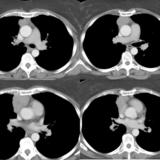

Case 8c Thymoma CT

Date: 03/27/2009

Views: 15482